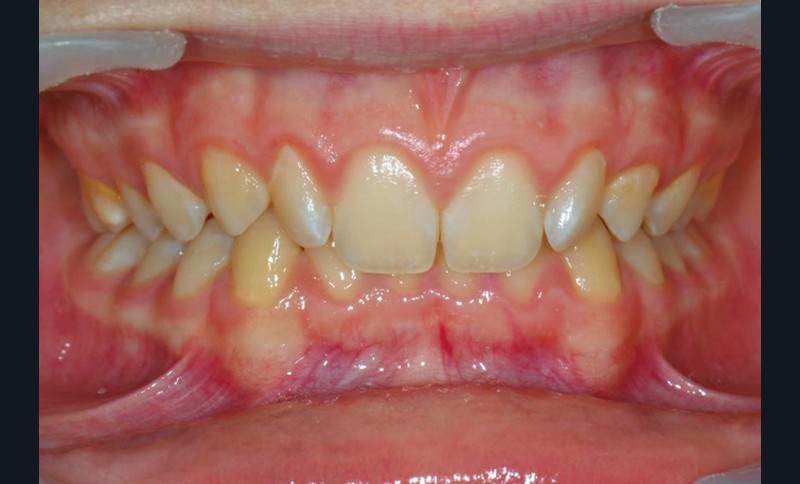

Son profil convexe s’inscrit dans un contexte de classe II squelettique par rétrognathie mandibulaire normodivergente sur un schéma de Classe II/2 avec supraclusion et encombrement modéré (fig. 1 à 7).

La formule dentaire est complète, avec un léger retard d’évolution des deuxièmes molaires (fig. 8).

Le parodonte est de type 1 selon la classification de Maynard et Wilson.